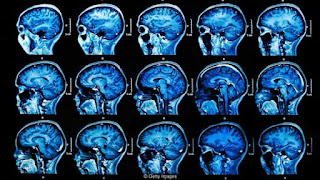

"The neat thing about music is it taps into a part of

your #brain that's often not touched as much by dementia,"